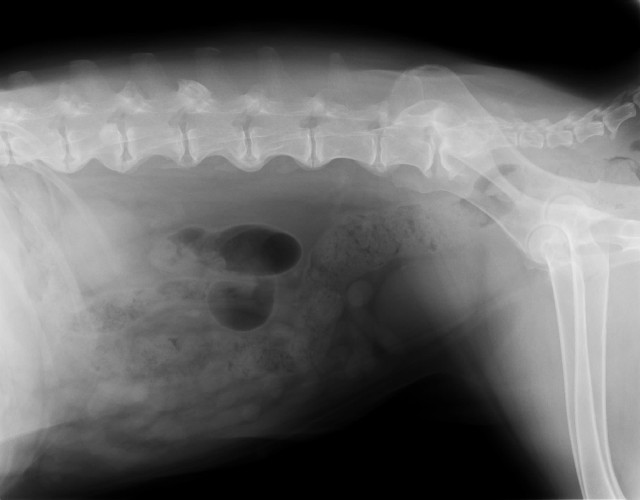

●レントゲンも3枚(胸・腰)撮りました。

うちの獣医さん、この秋にレントゲンをデジタル化したの。

だから、画像をCDに落としてもらえるようになったんだよヽ(*'0'*)ツ

キレイだからべべちゃんの“ヌード”3枚見てね。

診断としては、内臓関係は肺以外みんなOK(^^)v

肺は、べべは6歳半でうちに帰ってきた時にすでにフィラリアに罹っていて、肺に成虫が達していて、それを治療した残骸がある?し、フィラリアの影響か?肺のあちこちが石灰化してるの(前から)

背骨は変形性脊椎症であちこちブリッジにはなっているけど、これからも関節サプリ/アースリスージゴールドやマッサージやレーザーで手当てしてあげながら上手く着きあっていけば大丈夫♪